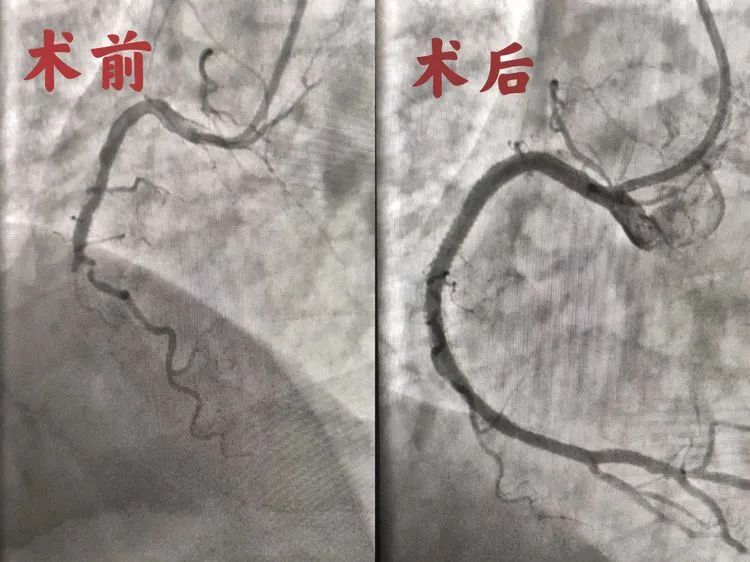

时间就是心肌,心肌就是生命。东方心内科团队立即为老人急诊行冠状动脉造影+植入术。造影提示:LM(-),LAD近中段斑块,50%狭窄;LCX(-);RCA中段支架内完全闭塞。面对狭长的梗塞位置,心内科团队明确定位后,凭借着熟练的操作,顺利将导管通过狭长的梗塞支架,由远及近续贯植入三枚药物涂层支架,手术顺利结束。